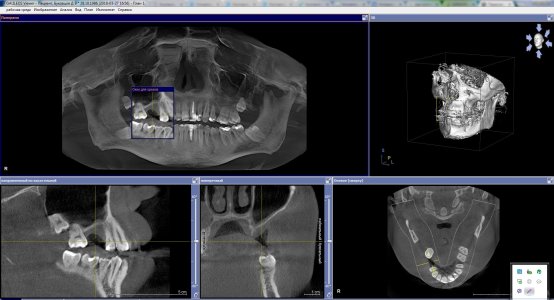

Прикладываю фото челюстно лицевой компьютерной томографии. Ссылка для скачивания архива самой томографии: https://cloud.mail.ru/public/3Bh2/J9rb61XX4 ( сделана в программе Galileos). Если нужно, могу выложить образ диска для виртуального привода.

20.01.18 удалил зуб у хирурга-имплантолога, с которым планировал дальше работать по имплантации. Договорись с ним, что я приду через 2 месяца, когда место удаления заживет и будем дальше решать что делать. Пришел к нему на приём 27.03.18, сделали челюстно-лицевую КТ, на основании которой он сказал, что собственной кости у меня, для вживления импланта очень мало (у меня где-то 1-2 мм, а нужно 6-8 мм толщины кости) и шансов на положительный исход операции по установке импланта (синус-лифтинг) немного. Посоветовал "смотреть" в сторону установки моста.